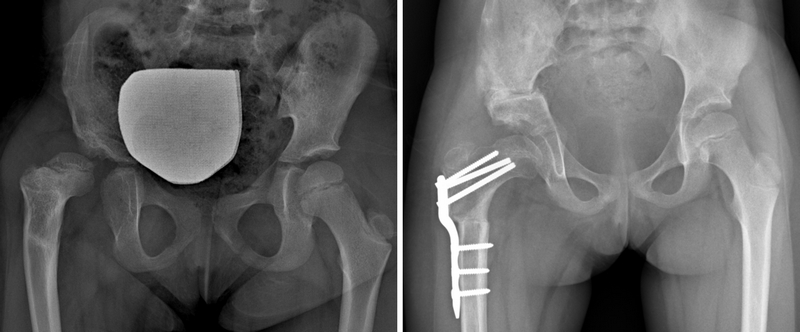

La tettoplastica ha come obiettivo quello di migliorare l’inclinazione del tetto e restringere l’acetabolo.

Per farlo, si esegue una osteotomia (=sezione dell’osso) subito sopra l’acetabolo, e si inserisce a questo livello un cuneo di osso come una zeppa, in modo da fare abbassare il tetto.

Il cuneo può essere preso dal paziente stesso o dalla banca dell’osso.

Viene eseguita un’osteotomia (=sezione dell’osso) del femore, l’osso viene piegato nella direzione corretta e fissato in modo che possa guarire nella giusta posizione.

L’osteotomia del femore può essere fissata con diverse modalità.

Un tempo utilizzavamo i puntali e i fili di Kirschner percutanei, cioè lasciati sporgere al di fuori della cute, al di sotto del gesso. Questo sistema però richiedeva lunghi tempi di immobilizzazione in gesso e lasciava cicatrici antiestetiche (infossate, ecc); in qualche caso poi i puntali non garantivano adeguata stabilità e si perdeva la correzione.

Per tale motivo questo sistema è stato ormai superato dall’utilizzo di placche metalliche più moderne che garantiscono più stabilità e riducono i tempi di immobilizzazione in gesso di questi bambini.

Questo è un aspetto da considerare per limitare al massimo il rallentamento dello sviluppo motorio di questi bambini.